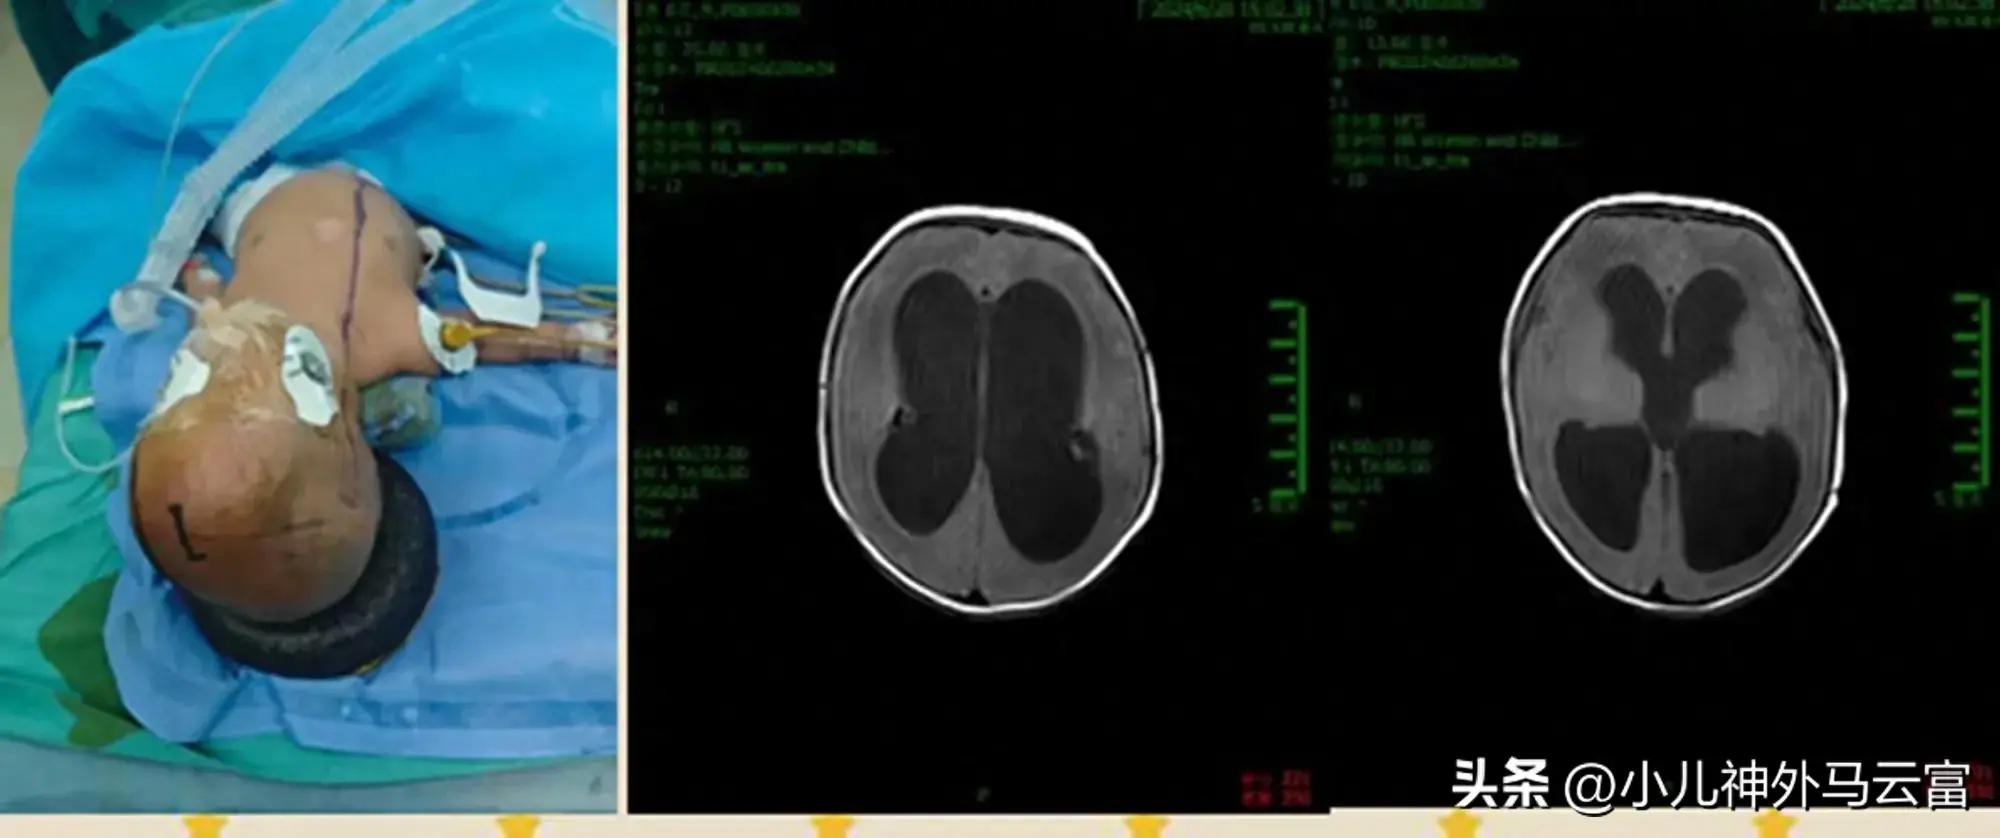

患兒小歐,因早產後腦出血,在新生兒科住院治療,治療期間寶寶頭圍逐漸增大,頭皮靜脈怒張,給患兒做了頭部核磁,提示:重度腦積水。

小歐:早產兒20日,1.2kg,重度腦積水

根據診斷結果,我們小兒神經外科團隊專家進行了多次討論,考慮患兒前期腦脊液化驗指標不達標,爲徹底解決問題,決定給予先進行腦室腹腔外分流術,持續引流、置換腦脊液,待腦脊液化驗指標達標後,再進行腦室腹腔內分流術,將分流管放入腹腔內,一勞永逸的解決腦積水問題。

2024.7.25CT腦室明顯縮小。

腦脊液檢查結果,逐步改善,效果顯著

繼續腦室腹腔外引流至2024年9月10日腦積水明顯減少,腦皮層明顯恢復增厚,腦脊液檢查3次正常後將腦室腹腔分流管引放入腹腔後10天左右傷口癒合,拆線痊癒回家,定期來我院複查調壓。術後1月病人來我院複查頭部CT見腦組織恢復,腦室明顯縮小,小孩恢復正常。

腦室腹腔內分流術後,腦脊液正常,腦室正常